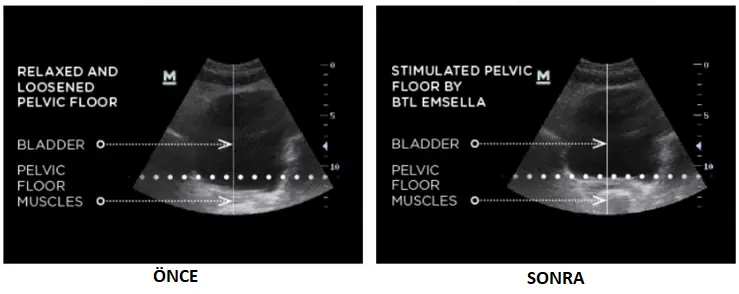

ÖNCE: Pelvik taban kasları pelvik organları yeterince desteklemiyor ve mesane kontrolü etkilenmektedir.

SEANS UYGULAMASI: Musplus-Chair, her seansta binlerce kasılma ile pelvik taban kaslarını etkili bir şekilde uyararak güçlendirmektedir.

SONRA: Stimülasyon, pelvik taban kasları ve mesane üzerindeki kontrolün yeniden kazanılmasına yol açar.